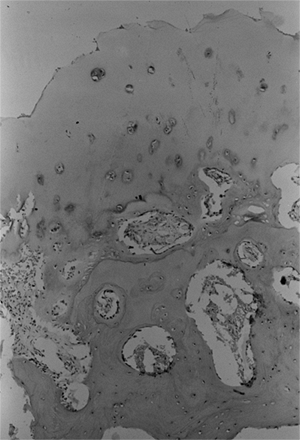

taken from both the proximal femoral physis and femoral neck in

patients with developmental coxa vara (12,34,40).

These have shown defects in cartilage production and secondary

metaphyseal bone formation in the inferior portion of the proximal

femoral physeal plate and adjacent femoral neck. The cartilage cell

numbers are decreased and the remaining cells are not well organized in

regular columns as seen in a healthy physis. The adjacent metaphyseal

bone is osteoporotic and infiltrated with nests of cartilage cells (34,40) (Fig. 27.8).

Figure 27.8

Photomicrograph of a biopsy specimen of the proximal femoral physeal plate of a patient with developmental coxa vara demonstrates irregularly distributed germinal cells in the resting zone; an absence of normal, orderly progression of the cartilage columns; and a poorly defined zone of provisional calcification. Nests of cartilage cells reside at the margin of the metaphyseal bone. |